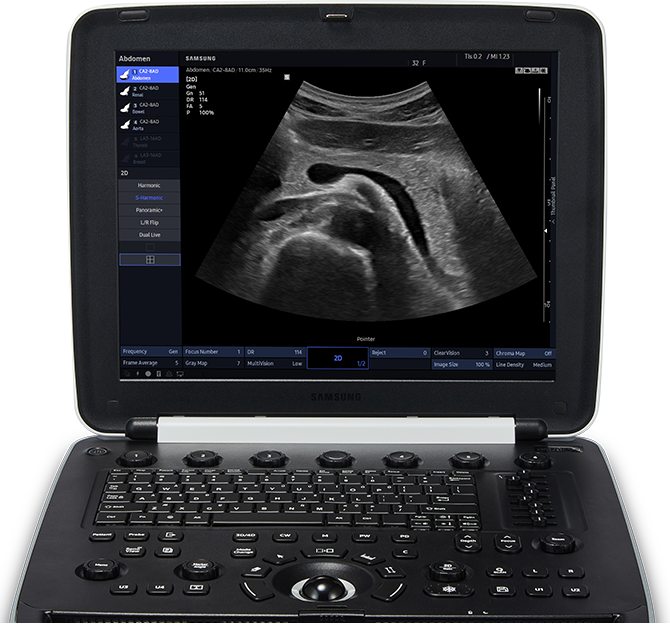

HM70 EVO

The HM70 EVO ultrasound system is a high-performance hand-carried ultrasound system, evolved to support a diverse range of applications and patients. The system has streamlined workflow, durability, and high resolution imaging that can be used in a variety of clinical situations. Samsung has harmonized the key aspects of the HCU to meet today's changing needs and provide healthcare professionals the confidence they need in their work environment.

Imaging with exceptional quality

Exceptional image clarity and penetration is adapted from Samsung's high-end imaging platform to produce clear, uniform, high resolution 2D and color images. The HM70 EVO delivers sophisticated imaging technologies to empower ultrasound professionals with diagnostic confidence wherever needed.